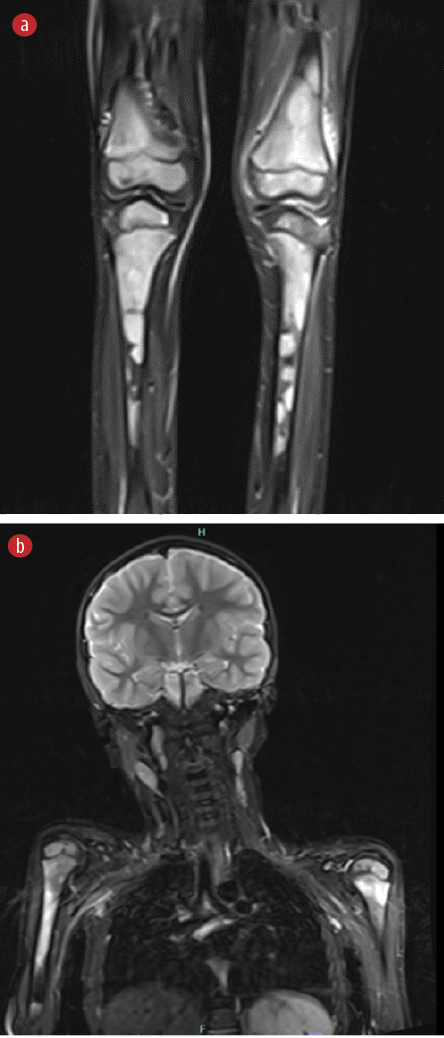

The patient’s whole-body magnetic resonance imaging (MRI) revealed multifocal heterogeneous areas of T2 hyperintensity affecting almost all bones, including the sternum, pelvis, and phalanges of the hands and feet. The left knee joint had a small effusion. Similar radiographic changes were observed in the humerus, radius, ulna, carpals, metacarpals, femurs, tibias, fibulas, tarsal, sternum, scapulae, clavicles, multiple spinal processes, posterior-superior iliac spines, iliac crests, and phalanges. Features were in keeping with those of chronic recurrent multifocal osteomyelitis (CRMO) [Figure 2].

Figure 2: Details from the whole-body MRI. Multifocal heterogeneous areas of T2 hyperintensity affecting mainly the long bones (epiphysis, metaphysis, and diaphysis, with affinity to metaphysis). Also, periosteal elevation and surrounding soft tissue edema at the distal left femur and proximal left tibia, with focal thinning of the cortex of the tibia. Small joint effusion of the left knee. The brain parenchyma is unremarkable.